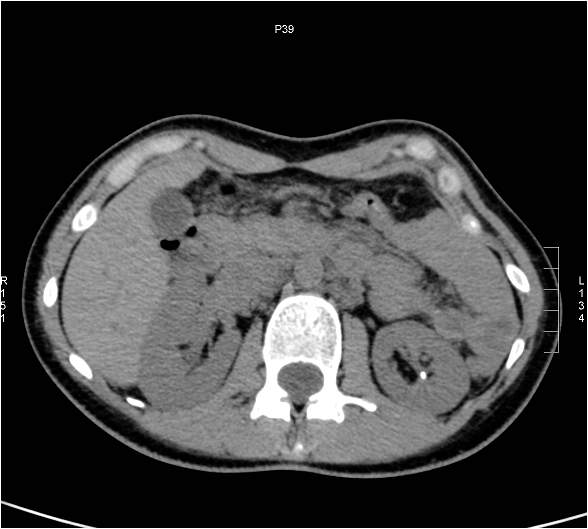

Image

Figure 12. Extensive right ovarian tumor.